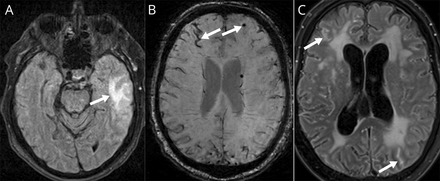

(一)T2 fluid-attenuated反转恢复图像显示左侧颞叶hyperintensity(箭头所指)。(B) Susceptibility-weighted图像显示microhemorrhages和表面的铁尘肺(箭头)。(C) 6个月gadolinium-enhanced T2 fluid-attenuated反转恢复显示leptomeningeal增强(箭头)。

一个73岁的老人突然出现右侧的弱点,失语症,轻度头痛。病史是阻塞性睡眠呼吸暂停相关,高血压、糖尿病、血脂异常,而他是适当的治疗,除了服用阿司匹林一级预防。初始的验血,头部CT和血管成像是正常的。MRI显示nonenhancing, nonrestricting T2 hyperintensity左颞叶,除了多个microhemorrhages (图1中,A和B)。解决在24小时内出现症状,出院第二抗血小板剂(氯吡格雷)。三个星期后,发生了第二集失语症和右侧的弱点,在数小时内解决。他回到医院的第二天,症状又复发。他一直不断地抱怨头痛,和他的家人已经指出过去一个月逐渐认知能力下降。重复的验血和红细胞沉降率是正常的。MRI显示持续的microhemorrhages和表面铁尘肺,左颞叶皮层下的变化,恶化以及。软脑膜显影并且

出院后6个月,混乱的进展,头痛加剧,促使回到医院病人步态开发困难。验血结果包括绝对中性粒细胞计数、甲状腺、肝、肾功能,和血清炎症标记物包括红细胞沉降率、抗核抗体,antineutrophil胞质抗体是正常的。传染病检查艾滋病,梅毒,莱姆莱姆疏螺旋体病是负面的。重复CSF分析了蛋白质高程为1.06 g / L,略低于之前;再一次,零总有核细胞或红细胞被检测到,细胞学是负数,CSF葡萄糖是正常的,分枝杆菌和革兰氏染色剂,真菌文化,文化是负的。打开脑脊液压力没有得到。克雅二氏症测试与CSF 14-3-3,τ,和端点quaking-induced转换试验呈阴性。血清和CSF多种自身免疫性抗体面板是负面的。重复CT胸部、腹部和骨盆是负的。MRI显示解决以前观察到左颞hyperintensity,但发展的一个新的左顶叶梗死瘀斑的出血,以及恶化leptomeningeal增强(图1 c)。